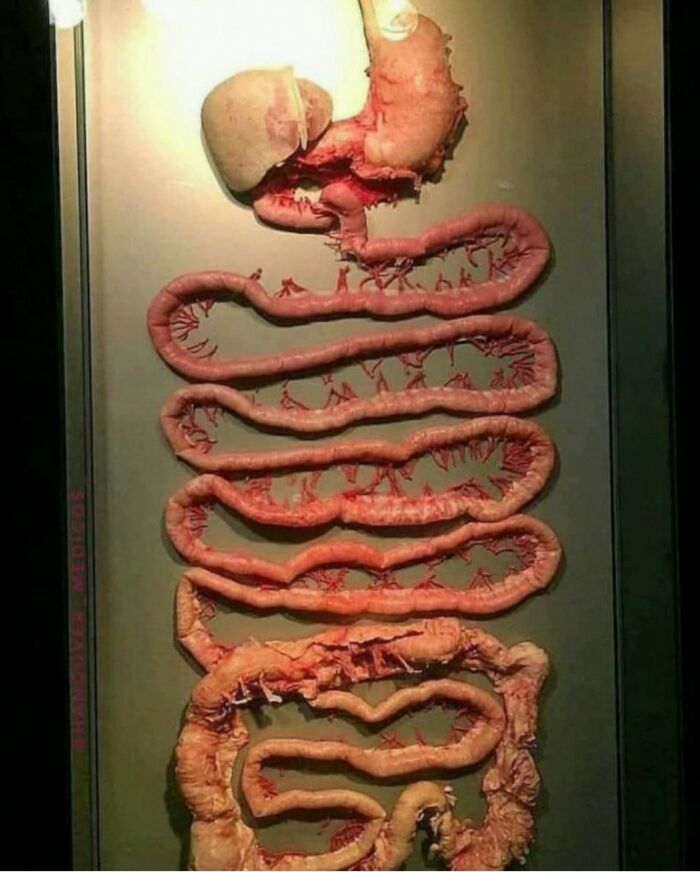

The entire human digestive system

Image credits: creepymedical